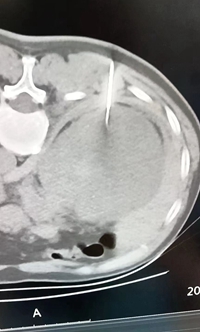

7月20日,我院多學(xué)科合作成功開展了一例CT引導(dǎo)下腎臟腫塊穿刺活檢術(shù),此次穿刺活檢術(shù)的成功是我院在腫瘤診治方面取得的又一大突破。該技術(shù)成功實施可為眾多疑診腫瘤的患者提供病理學(xué)依據(jù),使患者在后續(xù)治療方面更精準(zhǔn)、更有效。

CT引導(dǎo)下穿刺活檢術(shù),是在CT引導(dǎo)下局麻下用穿刺活檢槍取出少量組織進(jìn)行病理學(xué)分析,從而明確腫塊病理分型,以便制定及調(diào)整治療方案。該治療技術(shù)具有操作安全、定位準(zhǔn)確,創(chuàng)口微小等優(yōu)點。

該患者是我院腫瘤科的一位患者,住院后醫(yī)生對其病情和身體情況進(jìn)行了綜合評估,最終確定為其實施“CT引導(dǎo)下腎穿刺活檢術(shù)”。手術(shù)時間短,過程順利,術(shù)后生命體征正常。此前該類患者都需外出到上級醫(yī)院就診,該項技術(shù)的成功實施,使患者在家門口就可得到明確的診斷,減少了路途的奔波,也為患者減輕了經(jīng)濟(jì)負(fù)擔(dān)。